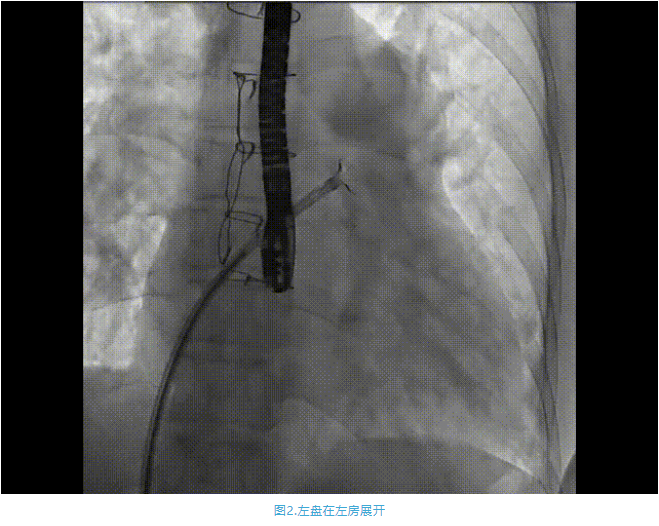

術(shù)中首先在局麻下穿刺股動脈、股靜脈,完成心導管檢查評估后轉(zhuǎn)為全麻,在食道超聲引導下穿刺房間隔,穿刺成功后將加硬導絲送入左上肺靜脈建立軌道,根據(jù)患者病情行球囊預擴張后植入6mm孔徑房間隔造孔支架,經(jīng)透視及食道超聲評估支架左右盤展開良好,夾持于房間隔兩側(cè),固定穩(wěn)定、位置良好,食道彩超顯示房水平右向左為主分流,分流孔直徑符合預期大小,心導管檢查評估達到預期效果,釋放造孔支架。術(shù)后12h患者下床活動,恢復順利,擬于近日完善術(shù)后評估后出院。